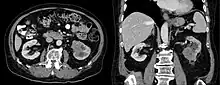

Collecting duct carcinoma in computed tomography